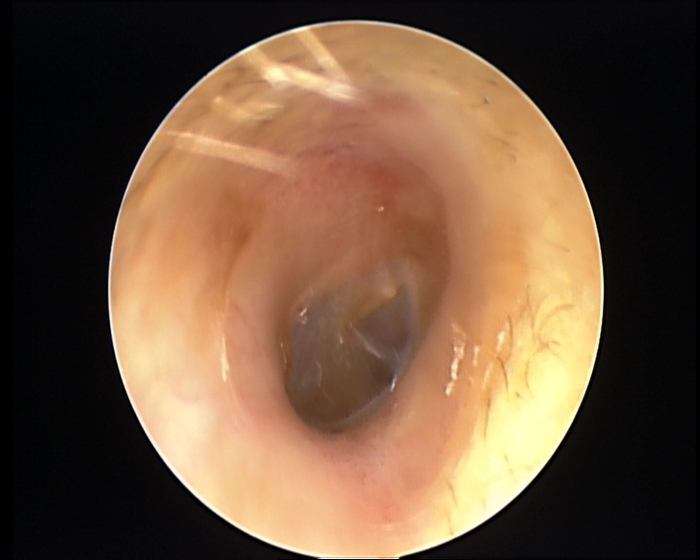

(提示:以下图片可能引起不适)

医生提供治疗图

医生检查发现,他的双侧耳道表面布满密密麻麻的白色绒毛物体,被诊断为“外耳道真菌病”。

治疗前